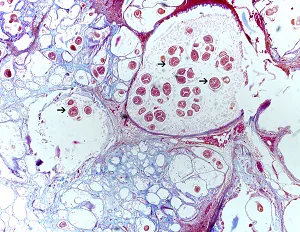

Echinococcus multilocularis in tissue.

Echinococcus multilocularis is the second most common cause of echinococcosis in humans. The definitive hosts for E. multilocularis are also canids, but more commonly foxes than domestic dogs. Arvicoline rodents (voles and related species) also play an important role in the natural life cycle as intermediate hosts.